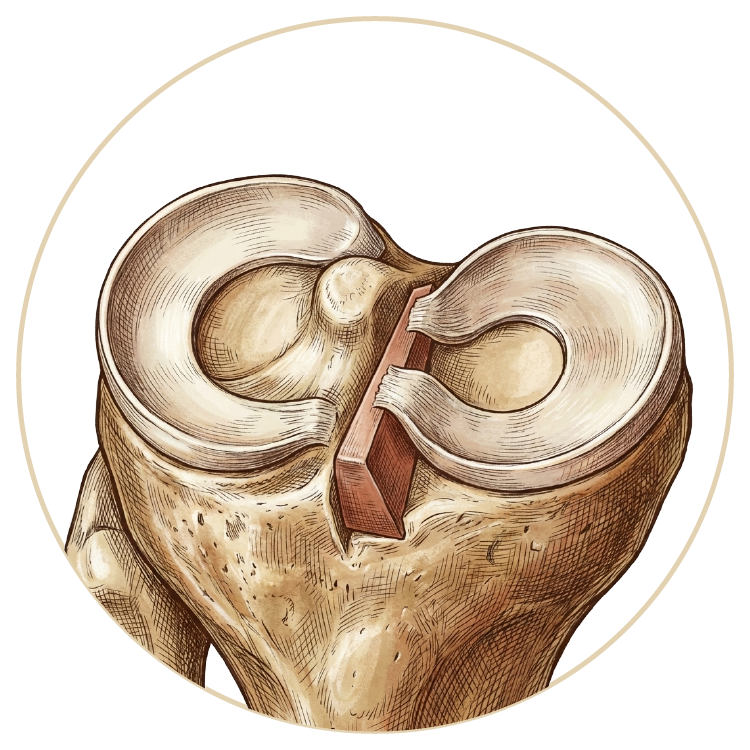

Menisküs Yırtığı

Menisküs Nakli

Kıkırdak Yaralanmaları